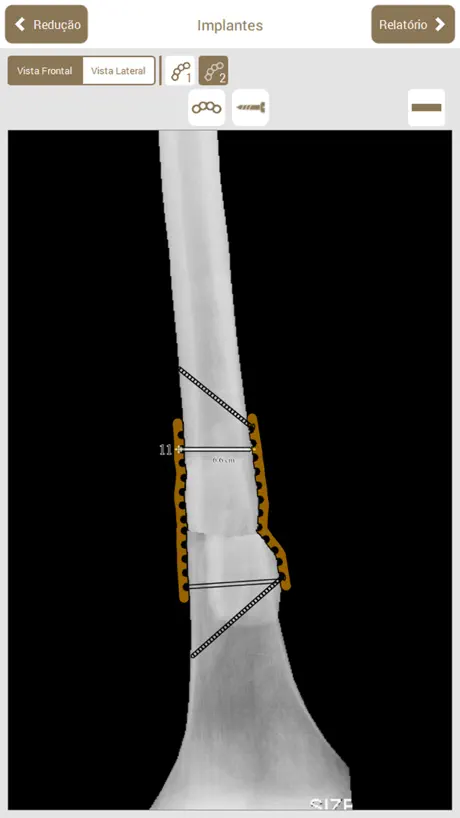

Osteotrauma é um aplicativo que auxilia no planejamento de cirurgias ortopédicas.

O objetivo do planejador é auxiliar o médico em todas as etapas do planejamento de cirurgias ortopédicas em fraturas de ossos longos.

No aplicativo, é possível executar os mesmos passos que são feitos em um planejamento manual: Escolha da radiografia, Classificação AO, Seleção e recorte das partes, Redução, Planejamento dos Implantes, Preenchimento da ficha do paciente, Geração de relatório e Edição manual do relatório gerado (que pode ser exportado em PDF).

O objetivo do planejador é auxiliar o médico em todas as etapas do planejamento de cirurgias ortopédicas em fraturas de ossos longos.

No aplicativo, é possível executar os mesmos passos que são feitos em um planejamento manual: Escolha da radiografia, Classificação AO, Seleção e recorte das partes, Redução, Planejamento dos Implantes, Preenchimento da ficha do paciente, Geração de relatório e Edição manual do relatório gerado (que pode ser exportado em PDF).